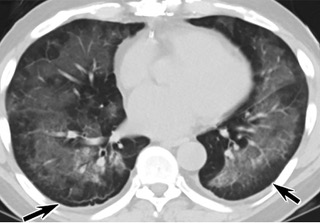

疑点一,电子烟患者的CT影像和临床表现并不具有特异性。所谓美国电子肺炎患者,其实是对没有其他合理诊断证据、吸食电子烟肺炎患者的统称。这些患者在病发前90天内吸食了电子烟,尤其值得注意的是,部分患者的CT影像特征和临床表现与病毒性肺炎患者极其相似。

中、下肺轴位CT平扫显示毛玻璃样混浊伴胸膜下保留。(同一病人CT影像)

中、下肺轴位CT平扫显示毛玻璃样混浊伴胸膜下保留(箭头)。(同一病人CT影像)